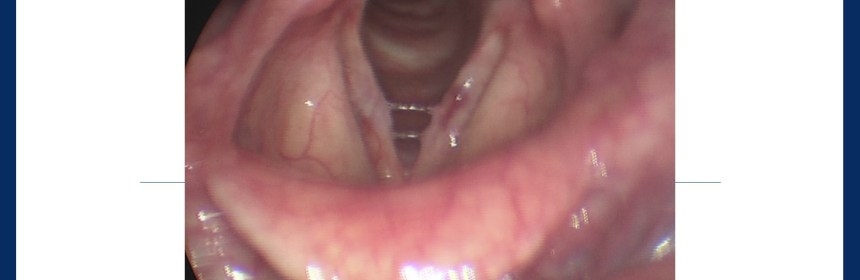

Mide içeriğinin ses oluşturan mekanizmalarla direkt teması anlamına gelen laringofaringeal reflüye özellikle önem gösterilmelidir. Toplumda yaygın olan kanı, reflünün ağıza acı su gelmesinden ibaret olduğu şeklinde olmakla birlikte, sessiz reflü aslında çoğu bireyi etkilemektedir. Bu durum, özellikle sık acılı yiyecekler tüketen ve domates bazlı soslar kullananlarda daha çok karşımıza çıkmaktadır. Reflü tanısının konması, hastaya herhangi bir zorluk getirmeksizin, rutin ses değerlendirme ekipmanları ile (videolaringoskopi) yapılabilmektedir. Reflünün ses kalitesi üzerine olan etkisi, yaptığımız klinik çalışmalar ile de objektif olarak ortaya konmuştur (H Oğuz, et al. Journal of Voice). Reflünün birçok belirtisi olmakla birlikte, ses profesyonellerine özgün olarak gördüğümüz belirtiler sabahları daha belirgin olan ses kısıklığı ve ses ısıtma süresinin uzamasıdır.